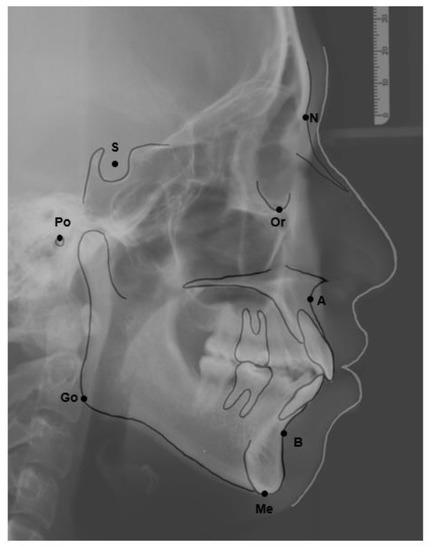

The skeletal relationship between the maxilla and mandible of orthodontic patients was categorized as Class I, Class II, or Class III [35,36,37,38] (Figure 1 and Figure 2). Steiner’s analysis [39] and Tweed analysis [40] were used for the measurements according to the analysis of St. Louis University in the United States, where the first author was trained for her orthodontic graduate program. The dental relationship between the maxilla and mandible of orthodontic patients was defined as molar Class I, Class II, or Class III (Figure 3). The DMFS index was expressed as the total number of teeth that were decayed (D), missing (M), or filled (F) in an individual with permanent dentition. There were five surfaces (facial, lingual, mesial, distal, and occlusal) for the posterior teeth and four surfaces (facial, lingual, mesial, and distal) for the anterior teeth when the DMFS index was calculated.

Figure 3. Angle’s classification of malocclusion. (a) Class I molar relationship: the mesiobuccal cusp of the upper first molar occludes the mesiobuccal groove of the lower first molar. (b) Class II molar relationship: the mesiobuccal cusp of the upper first molar occludes in front of the mesiobuccal groove of the lower first molar. (c) Class III molar relationship: the mesiobuccal cusp of the upper first molar occludes behind the mesiobuccal groove of the lower first molar.